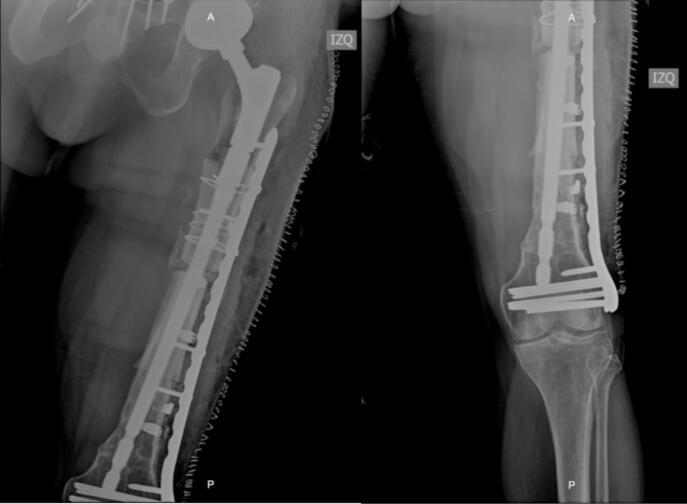

Defects in femoral bone segments represent a reconstructive challenge; they are caused secondary to multiple and extensive debridement in cases of patients with infections, tumors or high-energy trauma. Different treatments have been proposed to address this problem, however, these are limited when it comes to large defects that generate instability of the implants in the native bone as well as loss of functionality and length of the extremities. In the proximal femur, allograft prosthesis composites have been described in the management of extensive tumor resections, but they are not yet widely used in the management of bone defects due to osteomyelitis. The case of a 51-year-old male patient with post-traumatic pan-osteomyelitis of the femur Cierny-Mader IV with a 30-centimeter defect in whom limb salvage was achieved through the application of a femoral alloprosthesis is presented, exhibiting this surgical technique as an alternative in ample resections secondary to infectious processes in young patients, furthermore, offering a solution to the shortage of some prosthetic components in our surrounding.